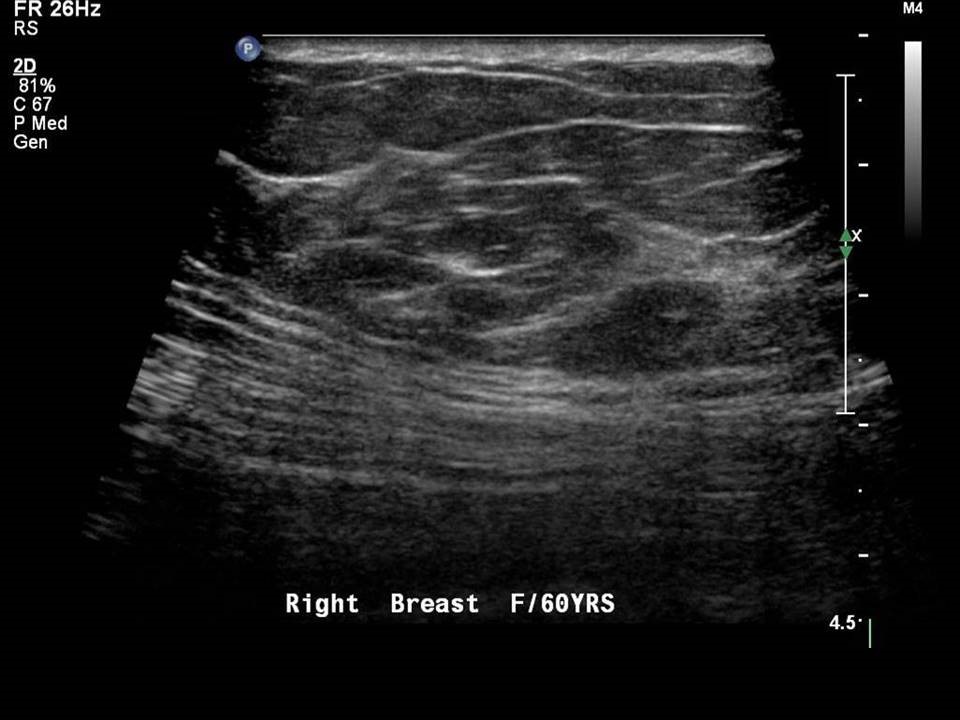

Breast USG

Breast ultrasound (USG) is a non-invasive imaging technique used to examine breast tissue for abnormalities such as lumps, cysts, or tumors.